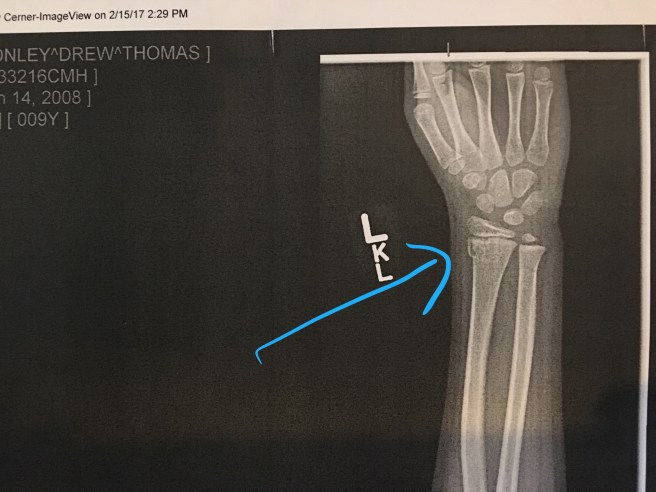

Drew has a shiny new cast (which will be dingy, dirty, and smelly next week probably).  You would think a hard cast would be worse than a splint, but in this case, no way!  This cast is about a quarter of the size of that ER splint he had for a week.  This morning we drove him up to the Children’s Mercy Clinic in the Northland on Barry Rd. which was the only location that could get us in promptly.  We had a fabulous experience there.  We met Dr. Kevin Latz who was very informative and reviewed both sets of x-rays with us.  He didn’t think there would be any impact on the growth plate and thinks he will heal just fine.  He suggested no sports until his wrist is fully healed and cast is off but he leaves it up to parents to decide.  Since this is our 6th broken wrist in the family we are feeling pretty confident that he can play soccer without a problem.

How do we fly down an icy mountain on 2 fiberglass sticks and make it out unscathed and 3 days later turn up with a broken wrist on flat ground!?  This poor guy was playing soccer at recess today and broke his fall with his left wrist.  A few hours later we found ourselves at Children’s Mercy getting x-rays and a splint.  Next week he will get a permanent cast.  This is brutal for a sports fanatic!  I think he’s already bored to tears and we’ve only been home an hour.  Diagnosis:   compaction fracture distal end of the left radius.  Once again…

2.15.17 Drew Left Wrist Fracture.jpg